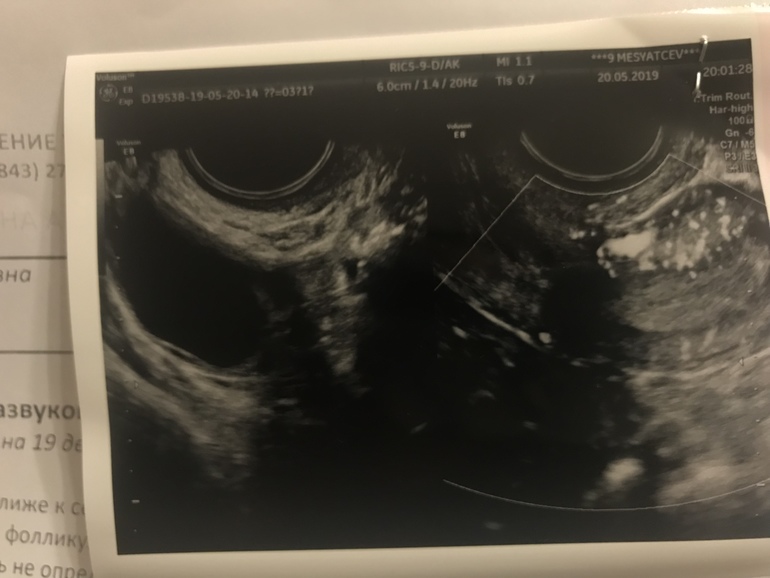

Фолликул или ЖТ?

ФолликулометрияБыла два раза на фолликулометрии. Узистка сначала подумала что ЖТ, потом сказала что фолликул все так.

А я вот до сих пор сомневаюсь ( девочки, кто разбирается , на что похоже ?

1 фото) 24 мм.. если жидкость в позадиматочном пространстве в незначительном количестве

2 фото) 30,5 на 17мм , сказали уже киста

Я не уверена, но вроде фолликул с чёткими краями, а жт с размытыми что-ли.. У вас везде вижу чёткие края, значит фолликулы